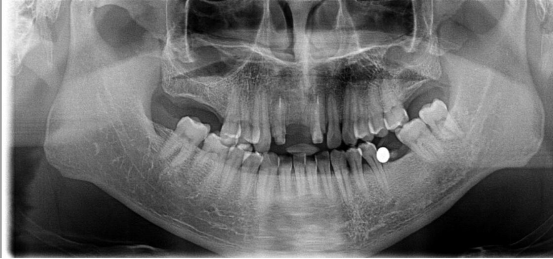

全口種植牙修復(fù)案例

病例簡介:

郭先生今年67歲,是位白手起家的成功企業(yè)家。早期忙碌的工作讓他疏于口腔保健,導(dǎo)致他上下牙列缺失。郭先生表示在二十年前在國外已經(jīng)做過種植牙,但是近期來我院就診時其之前種植牙的種植體已經(jīng)滑入到上頜竇內(nèi)。

“患者前牙骨量不足,壁薄,后牙因手術(shù)取出以前的種植體導(dǎo)致了骨頭的大量缺損,所以需要植骨才能進行種植牙手術(shù)。種植需要避開手術(shù)后的骨缺失區(qū),所以對種植體的承受力和穩(wěn)定性要求較高,同時患者對美觀要求較高?!眲⒈笤淌谠诹私饬嘶颊叩男枨笈c口腔情況后為他進行了植骨手術(shù),傷口愈合后,劉斌元教授為他進行CT掃描后確認(rèn)可以進行種植牙手術(shù)。

手術(shù)成功結(jié)束,郭先生的全口牙齒全部種上,郭先生表示種牙后感覺很好,使用起來很方便:“終于吃上了我喜歡的堅果了!”